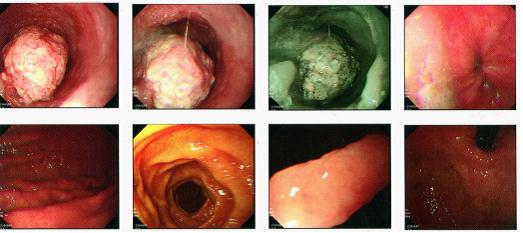

电子胃镜(图1):食管28-34cm见巨大肿物,似有亚蒂,表面溃烂,NBI示不均匀深染,细微结构欠清,取活检,粘膜光滑湿润,贲门闭合良好,胃底粘膜光滑,胃体脑回状,橘红色。胃窦粘膜欠光滑,蠕动正常,色泽白红相间。幽门可见,圆形,开闭自如,粘膜光滑,色泽淡红。十二指肠球部黏膜光滑,未见溃疡。球后未见异常。考虑:食管肿物性质待查,慢性胃炎

图1

活检病理提示:(食管)鳞状细胞癌(图2)